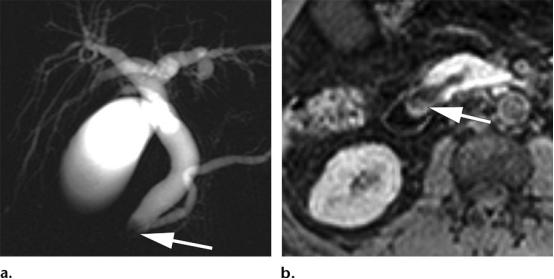

42岁男性,十二指肠乳头周围的腺瘤,(a图)磁共振胆胰管成像示胆道扩张,胰管扩张,以及胆总管远端边界不清的充盈缺损(白色长箭头),(b图)轴位增强T1WI示十二指肠乳头区域不均匀强化的结节样病变(白色长箭头)。

53岁男性,主胰管的导管内乳头状粘液性肿瘤,(a图)冠状位T2WI,示扩张的主胰管内低信号的充盈缺损影(白色长箭头),(b图)轴位增强T1WI示沿着扩张主胰管走形的结节样黏膜强化影(白色长箭头),(c图)内镜示十二指肠区域经典的鱼眼样外观,十二指肠大乳头突入十二指肠。